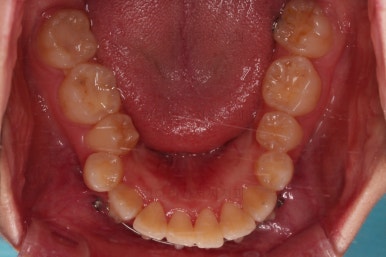

교합, 과개교합 모두 좋아졌고요.

발치 공간도 깔끔하게 닫히고 종료했습니다.